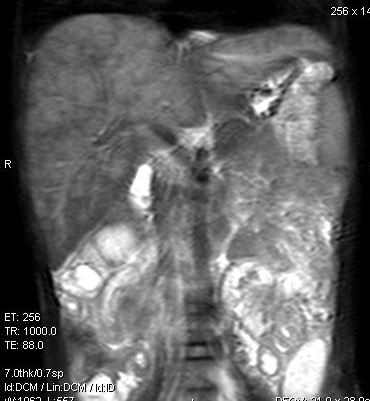

标题: V0176(MRI):小儿发热,肝脾大,肝内病变 [打印本页]

标题: V0176(MRI):小儿发热,肝脾大,肝内病变

5岁,2006年8月曾行阑尾炎手术,现发热半年